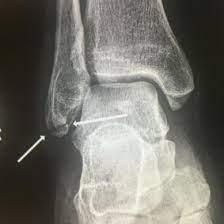

Een Weber A of avulsiefractuur komt vaak voor. Weber A is het uiterste deel van het kuitbeen. Een avulsiefractuur is een los botschilletje van een van de botten van uw enkel. Dit soort letsel aan het kuitbeen behandelen we op dezelfde manier als een scheur in de enkelbanden. U krijgt een drukverband of speciale kous (tubigrip) en een enkelbrace.

Een breuk aan het uiterste deel van het kuitbeen of een los botschilletje aan een van de botten bij u enkel komt vaak voor. U krijgt een drukverband of tubigrip. Dat is een soort kous. Ook krijgt u een enkelbrace. Zo heeft u minder pijn en geneest het letsel het snelst.